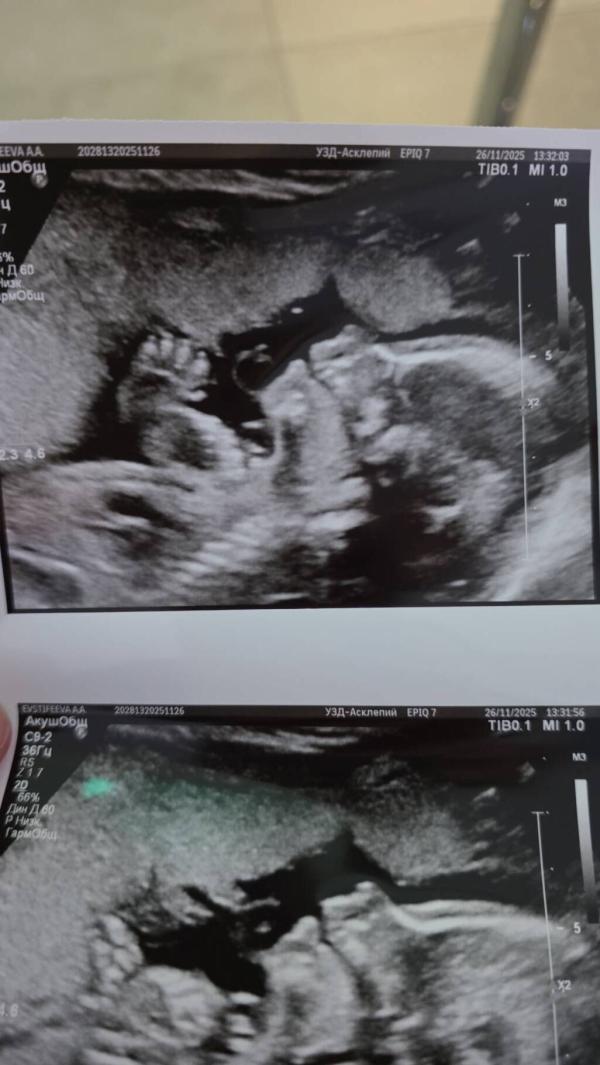

Второй скрининг позади, все хорошо. Мои болезни обошли малышку стороной. Слава Богу 🙏 почти экватор, но в эту беременность я совсем не тороплю время, столько дел и забот, что время само летит! Завтра переезд в наш дом, мы доделали основные этапы ремонта, можно будет после нового года начинать думать о детской, присматривать мебель для малышки. Впереди очень много интересного 🤗🥹